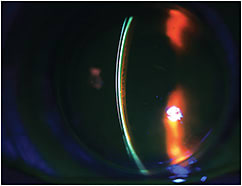

During Initial Dispense Empirically fit hybrid lenses for regular corneas, in which the GP center masks any underlying corneal astigmatism, are typically observed without the aid of NaFl. Predicted base curve calculations, in conjunction with an expected dioptric range for over-refraction, are markers for adequacy of fit. If NaFl is applied to the front surface of a hybrid lens that is fit on a regular spherical or astigmatic cornea, expect to see NaFl creep under the lens surface within the first minute of wear to highlight adequate tear exchange upon blink and a mobile lens. With fluorescein diluted in the layer of tears between the back of the lens and the front of the cornea, you will see a thin characteristic layer of NaFl under the GP center and a more intense NaFl ring at the GP/soft skirt junction corresponding to the clearance of the hybrid lens over the cornea (Figure 2).